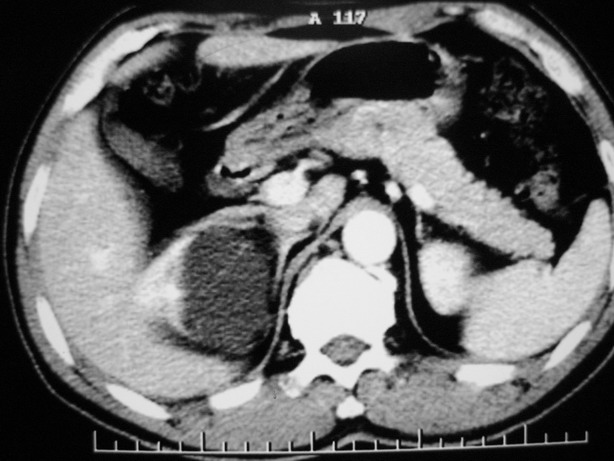

标题: CT10772:男性,48,右肾盂旁多囊性占位!

男性,48,体检发现,平时无症状。

平扫:

肾盂旁多囊性占位,有实性成分,增强有轻度强化,收集期病变内无造影剂显影。诊断肾盂旁囊肿,有实性成分无法解释,查书后诊断为:多房性囊性肾瘤!!不知大家同意否?????????对本病知道不多,望大家不吝赐教!!